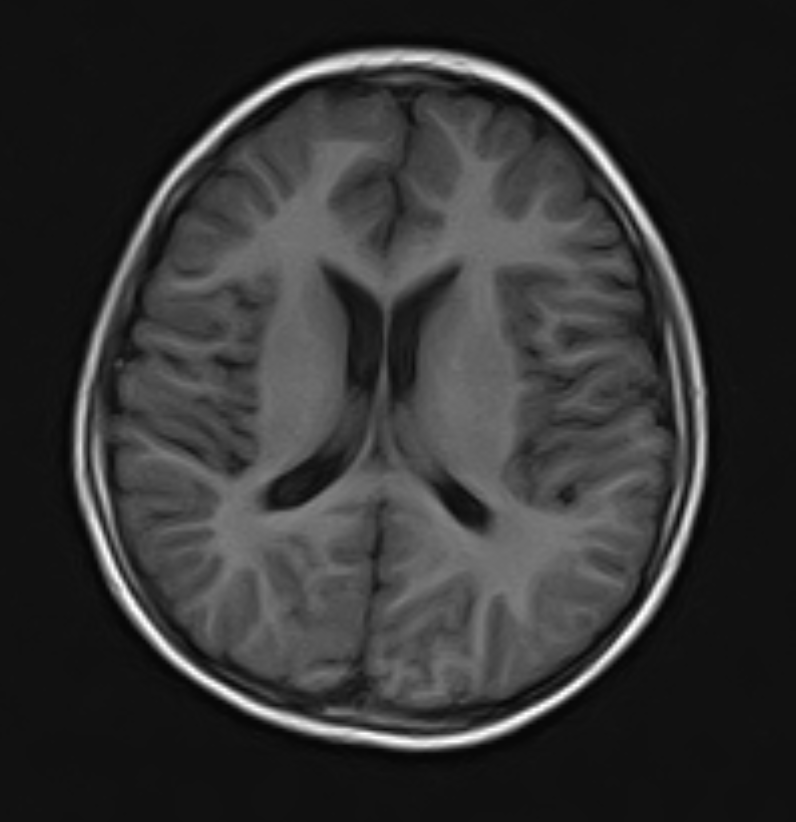

Take a pounding headache, for example. Sure, it’s often just a migraine, but sometimes it’s a warning sign for something far more serious — a brain bleed, a stroke, even a tumor. Strokes are a real headache (no pun intended) because they love to masquerade as each other. Ischemic or hemorrhagic, both can start with the same stuff: headache, a weak arm or leg, or suddenly losing coordination. It’s not always easy to spot the difference without the right evidence.

This is precisely where the CT scan machine steps in. In just a few seconds, it provides sharp, detail images of the brain. A hemorrhagic stroke will typically show up as a bright white area, while an ischemic stroke appears as a darker patch of compromised tissue. This obvious distinction allows physicians to spot the cause right away and initiate the correct, life-saving treatment — no waiting around.